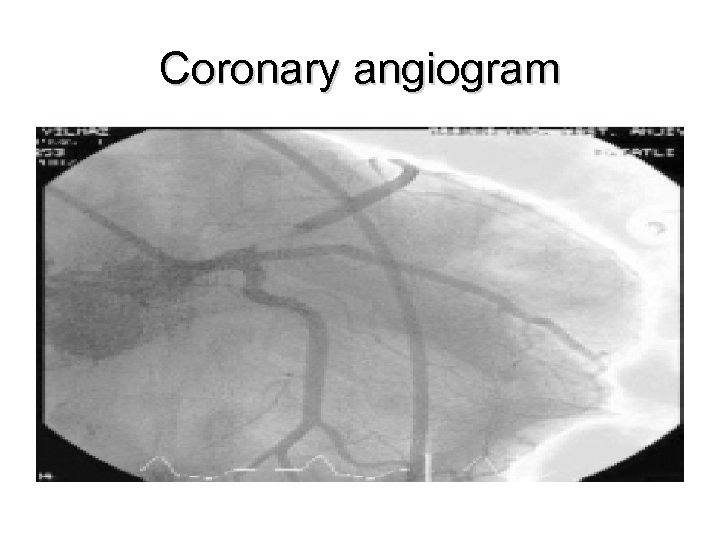

Coronary angiogram

Management • Diagnosed with Wellen’s Syndrome • Coronary angiogram showed 95% stenosis of LAD • Percutaneous angioplasty and stinting performed • Patient discharged 3 days later